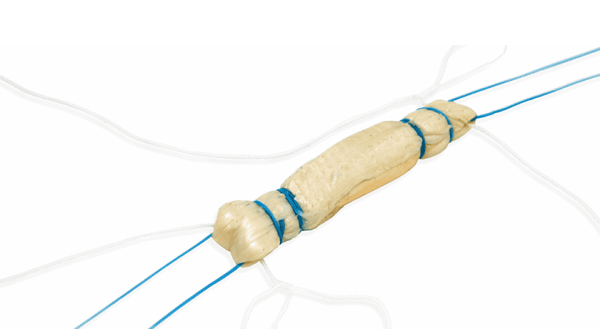

ReConnex is a ready-to-use, FDA 510(k)-cleared device designed to help simplify all-inside anterior cruciate ligament reconstruction.

Miach Orthopaedics initiated the Bridge Registry to assess real-world outcomes for the Bridge-Enhanced ACL Restoration (BEAR) Implant.